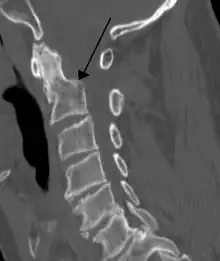

Fracture of dens

Repair of a dens fracture

Fractures of the dens, not to be confused with Hangman's fractures, are classified into three categories according to the Anderson Alonso system:

• Type I fracture - Extends through the tip of the dens. This type is usually stable.

• Type II fracture - Extends through the base of the dens. It is the most commonly encountered fracture for this region of the axis. This type is unstable and has a high rate of non-union.

• Type III fracture - Extends through the vertebral body of the axis. This type can be stable or unstable and may require surgery.